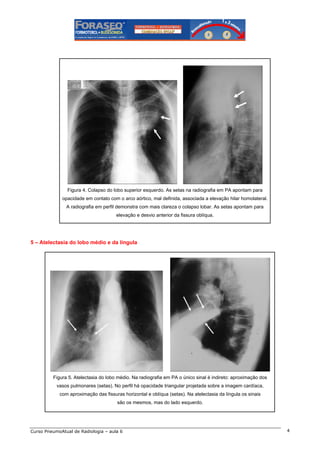

Figura 4. Colapso do lobo superior esquerdo. As setas na radiografia em PA apontam para

opacidade em contato com o arco aórtico, mal definida, associada a elevação hilar homolateral.

A radiografia em perfil demonstra com mais clareza o colapso lobar. As setas apontam para

elevação e desvio anterior da fissura oblíqua.